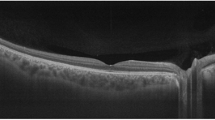

4.3 The Neuro-Retinal Rim

The most anterior part of ONH contains the RGC axons, which make up the neuro-retinal rim . Figure 6.7 shows a B-scan displaying the structures of the ONH from the internal limiting membrane to the anterior lamina cribrosa. The neuro-retinal rim is separated from the vitreous by the inner limiting membrane (ILM) of Elschnig. ILM is an objective inner boundary of neuro-retinal rim tissue that is consistently detected by SD-OCT. In order to avoid overestimation or underestimation, rim tissue must be measured in the correct geometric orientation. Ganglion cell axons may exit the eye almost parallel to the visual axis or even perpendicular to it. Significant errors in rim measurements can occur if the measurement plane is fixed.

The most anterior part of the optic nerve head contains the retinal ganglion cell axons, which make up the neuro-retinal rim. The neuro-retinal rim is separated from the vitreous by the internal limiting membrane. The Bruch’s membrane opening represents the outer border of the rim tissue (nerve fibers), which is represented as a yellow ring. BMO Bruch’s membrane opening, ILM internal limiting membrane

Because of the varying orientation of the RGC axons upon their entry into the neural canal relative to the BMO, Povazay et al. and Chen and collaborators proposed that the minimum distance from BMO-RPE complex to the ILM represents the most accurate measurement of the axonal content in the neuro-retinal rim [13, 14]. The BMO is currently used as a reference by Spectralis OCT and the rim width is quantified as the minimum distance between the BMO and the internal limiting membrane. Chauhan and Burgoyne subsequently suggested using the end of the Bruch’s membrane proper for this purpose and explored the difference between this measurement, termed BMO-minimum rim width (BMO-MRW) and conventional measurements, called horizontal rim width (BMO-HRW), and demonstrated the superiority of the BMO-MRW measurements (Fig. 6.8) [11, 15]. Strouthidis and associates showed the utility of BMO-MRW for detection of progressive ONH change in experimental primate glaucoma [9].

The minimum distance from the Bruch’s membrane opening to the internal limiting membrane represents the most accurate measurement of the neuro-retinal rim width. BMO Bruch’s membrane opening, BMO-MRW Bruch’s membrane opening-minimum rim width, BMO-HRW Bruch’s membrane horizontal rim width, ILM internal limiting membrane